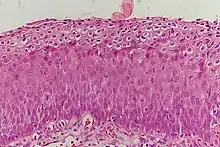

_normal_squamous_epithelium.jpg.webp)

Historically, abnormal changes of cervical epithelial cells were described as mild, moderate, or severe epithelial dysplasia. In 1988 the National Cancer Institute developed "The Bethesda System for Reporting Cervical/Vaginal Cytologic Diagnoses".[12] This system provides a uniform way to describe abnormal epithelial cells and determine specimen quality, thus providing clear guidance for clinical management. These abnormalities were classified as squamous or glandular and then further classified by the stage of dysplasia: atypical cells, mild, moderate, severe, and carcinoma.[13]

CIN is classified in grades:[14]

| Histology Grade | Corresponding Cytology | Description | Image |

|---|---|---|---|

| CIN 1 (Grade I) | Low-grade squamous intraepithelial lesion (LSIL) |

|

| CIN 2/3 | High-grade squamous intraepithelial lesion (HSIL) |

| CIN 2 (Grade II) |

| CIN 3 (Grade III) |